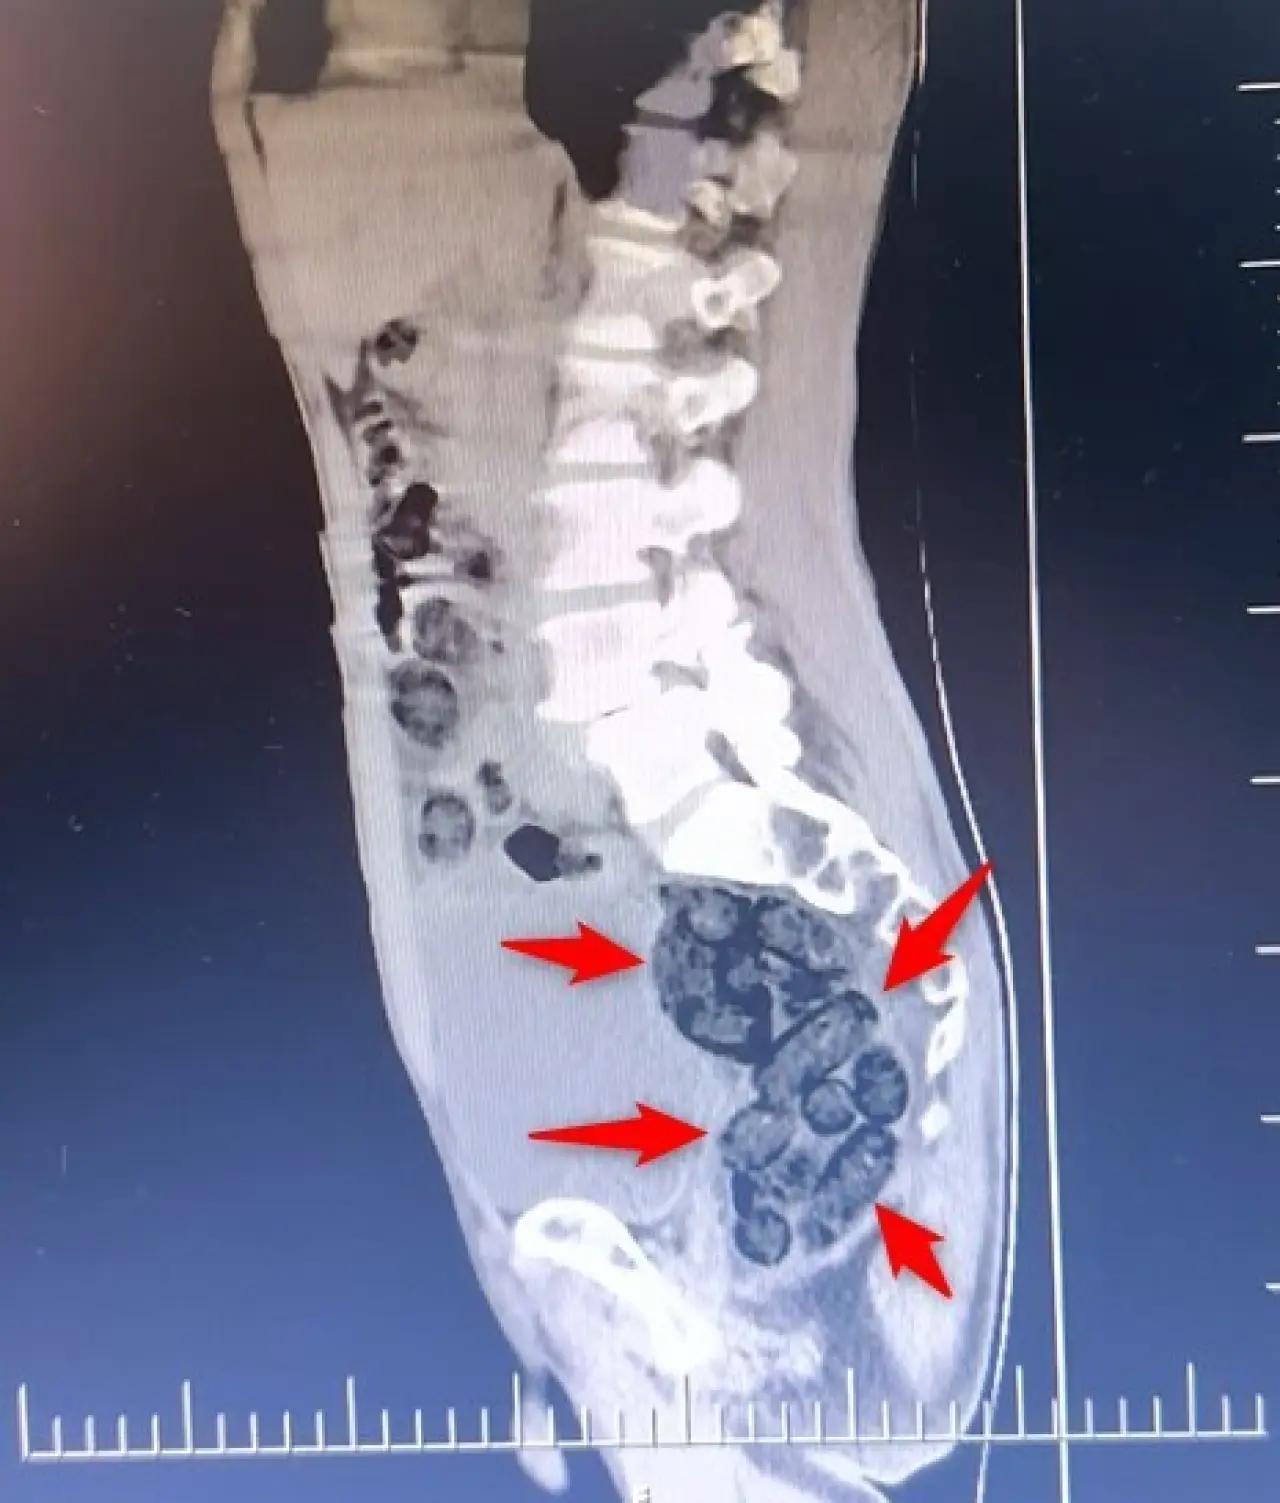

Batman’da durdurulan otobüste midesinden 64 parça metamfetamin çıkan yabancı uyruklu yolcu, polis operasyonuyla yakalanarak tutuklandı.

Batman’da durdurulan otobüsteki yabancı şahsın midesinden 64 parça uyuşturucu maddesi metamfetamin çıktı.

Batman İl Emniyet Müdürlüğü Narkotik Suçlarla Mücadele Şube Müdürlüğü ekiplerince Batman Cumhuriyet Başsavcılığı koordinesinde yürütülen çalışmalar kapsamında Batman girişinde durdurulan otobüste arama yapıldı.

Durumundan şüphelenilen yabancı uyruklu bir yolcu üzerinde arama yapıldı. Yapılan incelemeler sonucunda yabancı uyruklu şahsın midesinde 64 Parça halinde toplam 472 gram uyuşturucu maddesi metamfetamin olduğu belirlendi.

Gözaltına alınan şahsın midesindeki uyuşturucu madde çıkartıldı.